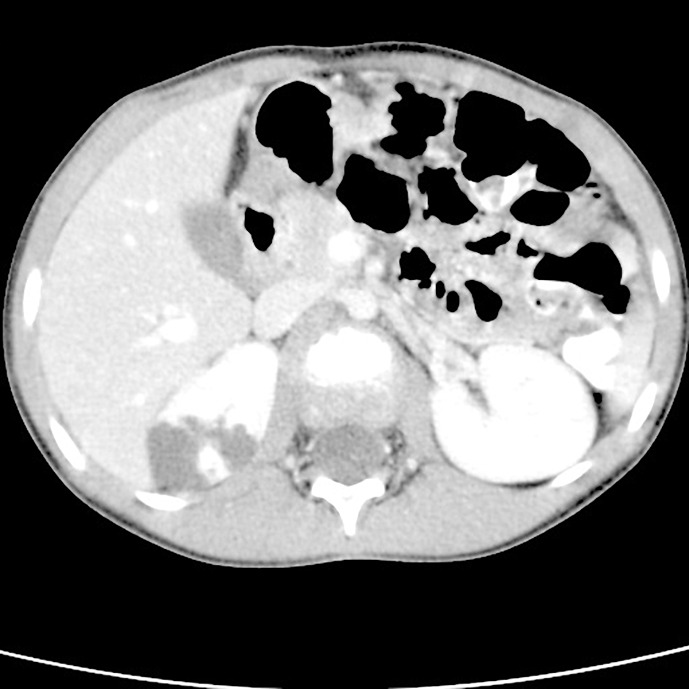

Case report: In a 6-year-old girl examined for abdominal pain, a cystic mass in the upper part of the right kidney was detected during an abdominal ultrasound. She was referred to pediatric oncology and urology for suspicion of a tumorous mass and the condition was assessed as a cystic nephroma. A heminephrectomy was then performed on the upper cystic part of the right kidney. The histological examination was inconclusive; therefore, genetic testing was recommended. Kidney and liver cysts were detected sonographically in the mother, but DNA analysis of the PKD1 and PKD2 genes did not reveal any pathogenic variant; the cause of the pathological formation in the kidneys remained unclear. Nine years later, next-generation sequencing of a panel of genes for kidney disease was performed and a heterozygous deletion was found on chromosome 16; this included exon 13 of the IFT140 gene. The same deletion was found in the patient's mother. Currently, the patient is 14 years old and has mild sonographic findings, normal glomerular filtration, mild proteinuria, and hypertension.